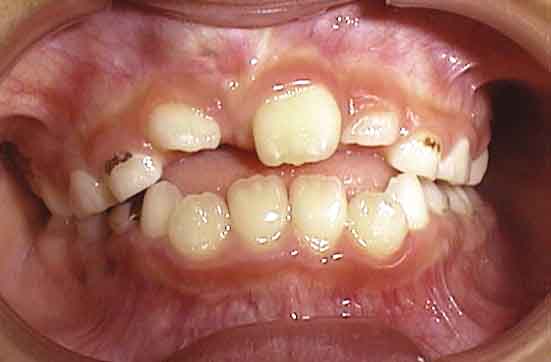

初診の状態